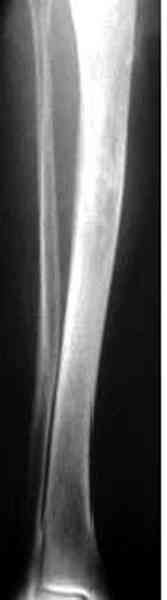

К нашему онкологу-ортопеду обратился больной с жалобами на боли в голени, из рассказа - год назад была сделана биопсия большеберцовой кости, но название заболевания "не запомнил”.

В литературе "A Classic Adamantinoma Arising from

Osteofibrous Displasialike Adamantinoma in the Lower Leg: A case report and Review of the Literature похожие снимки.